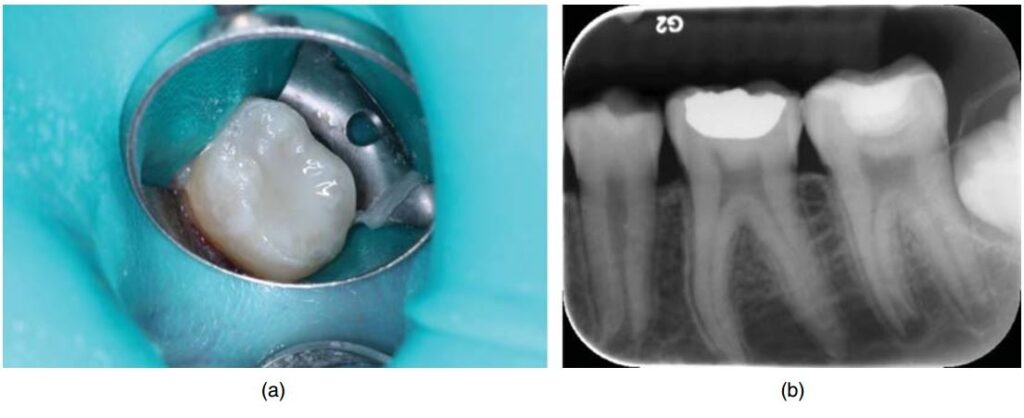

Sau khi khám và đánh giá X quang kĩ lưỡng (H10.3) thì thực hiện gây tê, đặt đê (H10.4).

Sử dụng mũi 557 hoặc 330 để mở rộng xoang sâu. Sau khi mở rộng, loại bỏ ngà sâu bằng mũi tròn #8 tay khoan chậm (H10.5).

Đặt thuốc (canxi hydroxit và GI) sau đó trám kết thúc (H10.8).